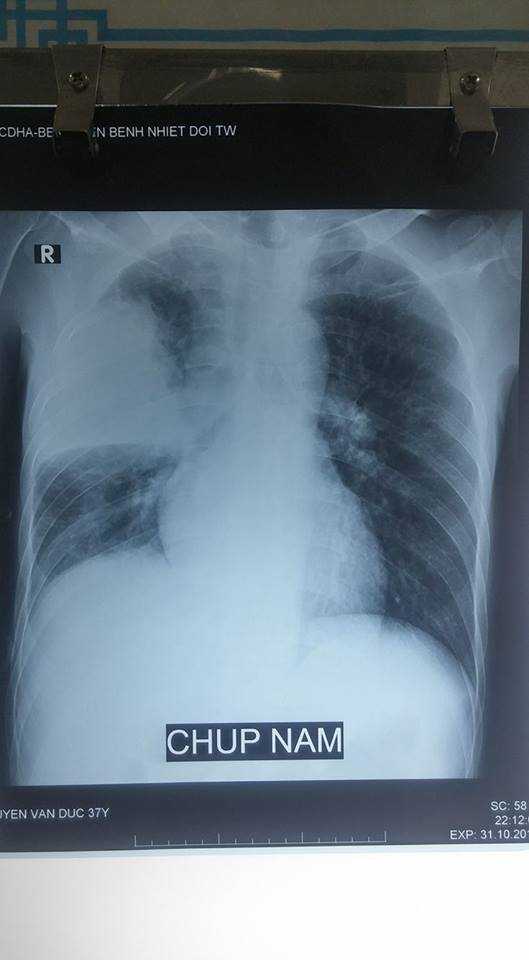

Mới gần đây, Khoa tiếp nhận bệnh nhân Nguyễn Văn Đ. ở Hưng Yên bị chứng viêm phổi do nghiện rượu. Mặc dù mới 39 tuổi nhưng anh Đ. đã nghiện rượu hơn 15 năm. Khi vào viện, bệnh nhân trong tình trạng tổn thương phổi, suy hô hấp nặng và có sốc nhiễm trùng. Hiện, anh Đ. Vẫn phải hồi sức tích cực.

Phim chụp Xquang phổi của bệnh nhân nghiện rượu.